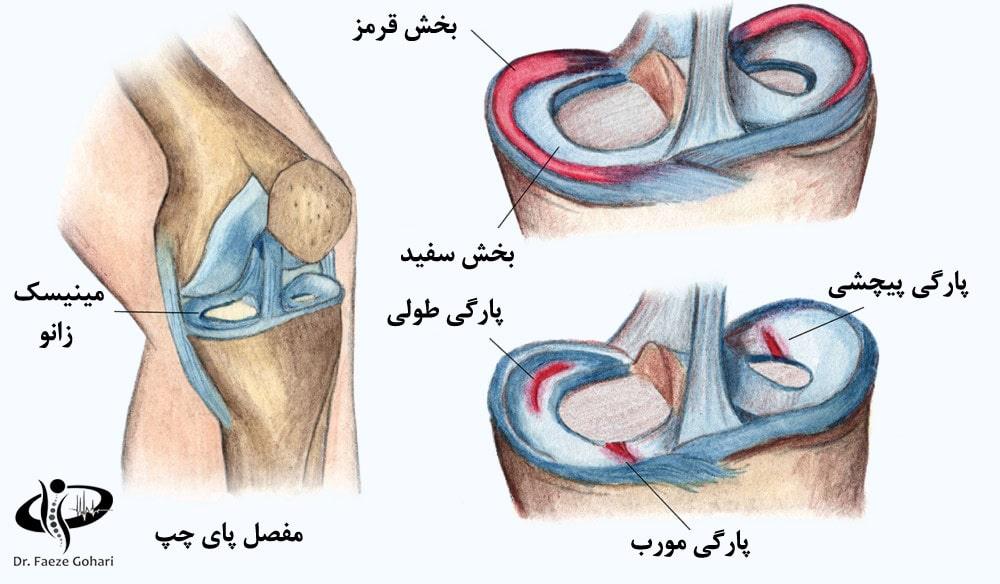

مینیسک زانو از دو بخش اصلی تشکیل شده: بخش خارجی (قرمز) و بخش داخلی (سفید). بخش خارجی مینیسک به دلیل رگهای خونی فراوان دارای خونرسانی بهتری است و بنابراین ترمیم آن سریعتر انجام میشود، درحالیکه بخش داخلی خونرسانی کمتری دارد و ترمیم آن دشوارتر است.

وقتی این بافت دچار پارگی میشود آسیب آن نیز به انواع مختلفی تقسیم میشود: پارگی طولی (Longitudinal)، پارگی افقی (Horizontal)، پارگی مورب (Oblique)، و پارگی پیچشی (Radial). هرکدام از این آسیبها میتوانند علائم و شدت متفاوتی داشته باشند و بسته به محل ایجاد، روشهای مختلفی برای درمان آن لازم است.

تزریق کوکتل سلولهای بنیادی همراه با پی آر پی برای درمان پارگی مینیسک معمولاً در پارگیهای عمقی و در نواحی داخلی با خونرسانی ضعیف، مانند بخش سفید مینیسک، مؤثرتر است. تزریق پی آر پی بهتنهایی ممکن است در ترمیم پارگیهای سطحی و غیر عمقی مخصوصاً در بخش قرمز مینیسک مؤثر باشد، اما وقتی که با سلولهای بنیادی ترکیب شده و تزریق میشود، اثرات بهبود بخش آن افزایشیافته و ترمیم بافتهای آسیبدیده با خونرسانی کم را نیز به طور قابلتوجهی تسریع میکند. در این روش، پی آر پی با ترشح فاکتورهای رشد، محیط مناسبی برای سلولهای بنیادی فراهم میآورد تا به طور مؤثرتری به غضروف و بافت آسیبدیده تبدیل شوند و روند ترمیم را تسریع کنند؛ بنابراین، تزریق سلولهای بنیادی همراه با پی آر پی برای پارگیهای عمقی و شدید مینیسک، گزینهای مؤثر و مناسب است.